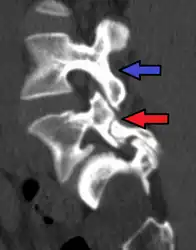

Anterolisthesis L5/S1 -

Anterolisthesis L5/S1. Blue arrow normal pars interarticularis. Red arrow is a break in pars interarticularis -